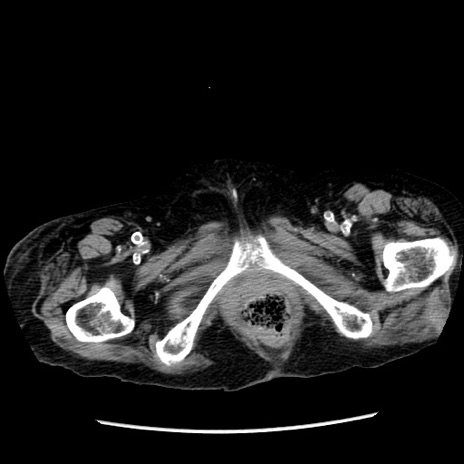

症例14(横断像)

【症例】 90歳代女性

【主訴】 腹痛・嘔吐

【現病歴】今朝から左側腹部痛を認めた。 経過観察していたが、嘔吐を認めたため来院。

【既往歴】 子宮癌術後

【身体所見】 意識清明、BP 127/54mmHg、P 98bpm Sp02 95%(RA)、BT 35.8°C、腹部平坦・軟腸ぜん動音聴取良好、右下腹部圧痛(+) 反跳痛なし

【データ】WBC 9800、CRP 0.46